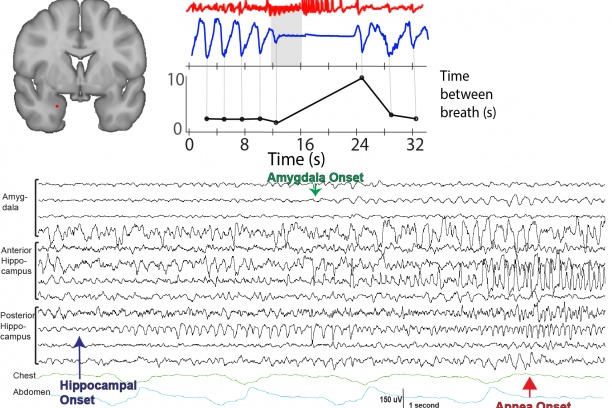

Sudden unexpected death in epilepsy (SUDEP), the enigmatic pathology whereby epileptic patients are found to have died without another cause, is the most frequent cause of death in epilepsy patients. The rare cases of SUDEP in healthcare settings show a sequence where apnea precedes terminal cardiac arrhythmias, implicating death due to respiratory decline. From our work and the work of others, it is clear that the amygdala has an underappreciated role in breathing. Our research aim is to investigate these brain regions through multidisciplinary approach to determine their role in epilepsy, apneas, and SUDEP.